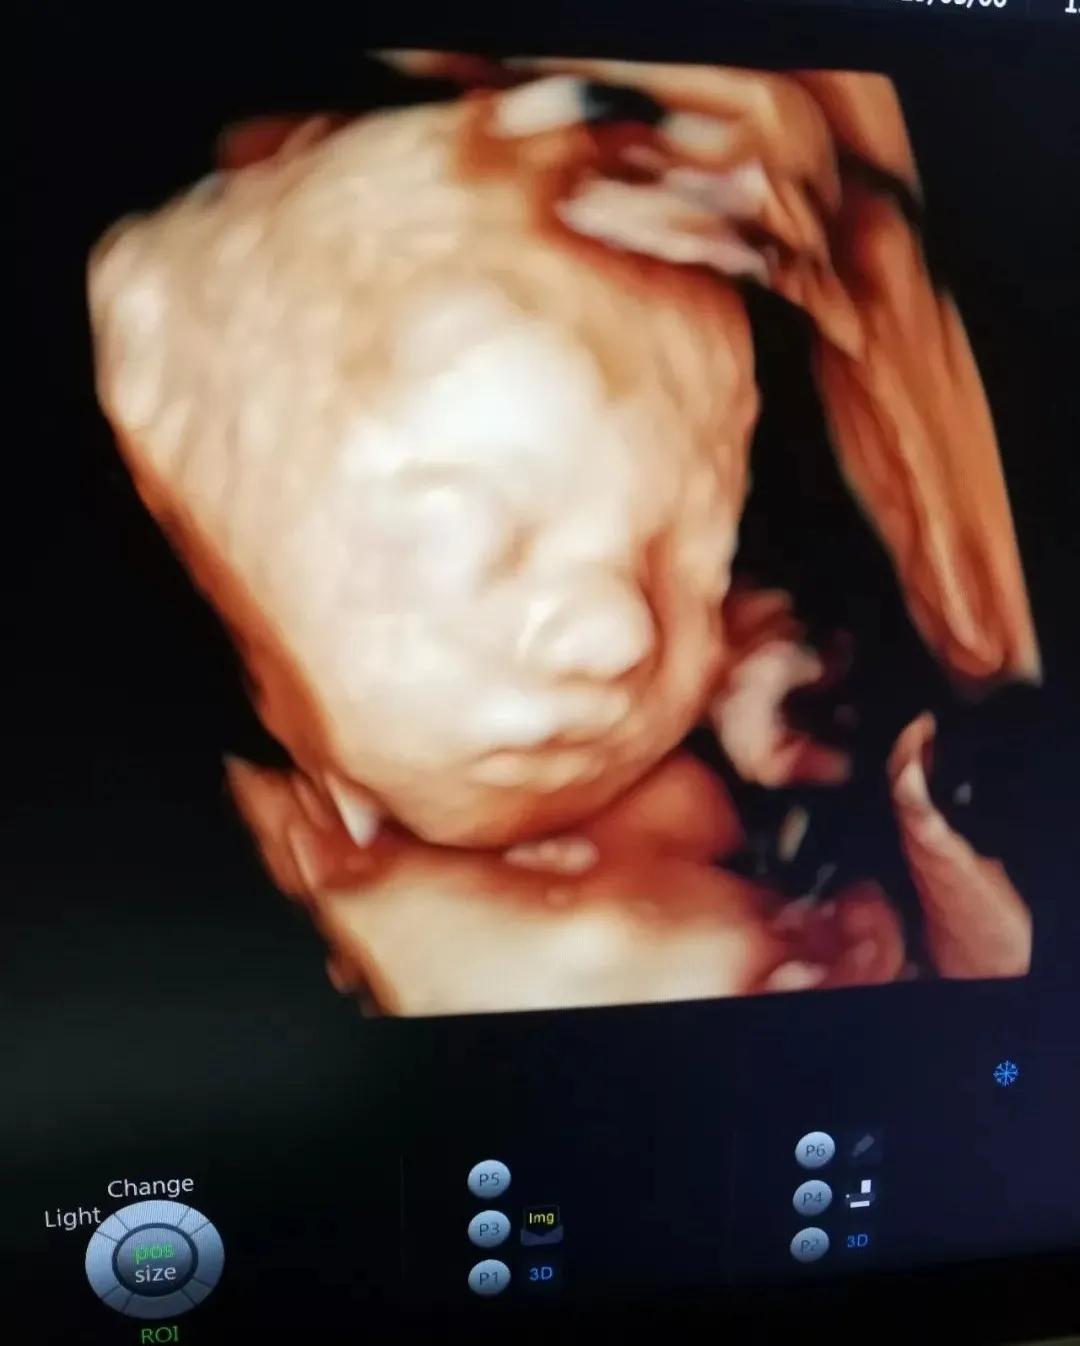

与胎宝紧密相连280天里,一次次胎动是你们之间独特的交流方式,而这时,我们更加好奇胎宝每天都在妈妈肚子里干什么呢?看看这些四维彩超抓拍的胎宝的小模样吧!以下为胎宝的自白时间哦~!

“Hi,妈妈,第一次看到我是不是很惊喜,很幸福~

在刚刚医生阿姨为我做检查时,我能感受到您一直紧绷着,所以,当听见您要见到我第一面的时候,我要送给您一个我的招牌动作~还告诉您一个秘密哦~知道您们在看我,我也很开森~”

也许肚子里的宝宝

还不能说TA们对妈妈的爱

但通过美琳达的四维彩超画面中

TA们的活泼好动,萌萌的表情

已经说明了一切